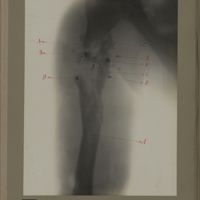

0116 - Page 4 - [Radiographie du thorax et de l'épaule]0116 - Page 4 - [Radiographie du thorax et de l'épaule]

0122 - Page 10 - [Radiographie de l'épaule et du thorax]0122 - Page 10 - [Radiographie de l'épaule et du thorax]

0172 - Page 60 - [Radiographie de l'épaule et du thorax]0172 - Page 60 - [Radiographie de l'épaule et du thorax]

0194 - Page 82 - [Radiographie de l'épaule]0194 - Page 82 - [Radiographie de l'épaule]